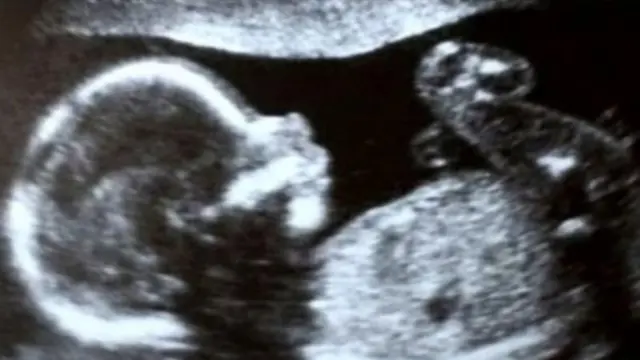

તાજેતરમાં જન્મેલું એક શિશુ એક મૃત દાતાના ટ્રાન્સપ્લાન્ટ કરવામાં આવેલા ગર્ભાશયમાં જન્મનારું બ્રિટનનું પ્રથમ બાળક બન્યું છે.

ઉંમરની ત્રીસીએ પહોંચેલાં ગ્રેસ બેલનો જન્મ ગર્ભાશય વિના થયો હતો. તેઓ કહે છે કે, હવે 10 સપ્તાહનો થઈ ગયેલો તેમનો પુત્ર હ્યુગો "સ્વયં એક ચમત્કાર છે."

2025ની નાતાલની બરાબર પહેલાં પશ્ચિમ લંડનની ક્વેન શેર્લટ્સ ઍન્ડ ચેલ્સી હૉસ્પિટલમાં હ્યુગોનો જન્મ થયો હતો. જન્મ સમયે તેનું વજન આશરે સાત પાઉન્ડ હતું.

બેલનો જન્મ ગર્ભાશય વિના થયો હતો અને તેમને માસિક પણ નથી આવતું, પણ તેમનાં અંડાશય સામાન્ય છે. આ સ્થિતિ એમઆરકેએચ સિન્ડ્રોમ તરીકે ઓળખાય છે, જે બ્રિટનની પ્રત્યેક 5,000માંથી એક મહિલામાં જોવા મળે છે.

બેલનું ગર્ભાશય પ્રત્યારોપણનું ઑપરેશન 10 કલાક સુધી ચાલ્યું હતું. આ ઑપરેશન જૂન, 2024માં ઑક્સફર્ડસ્થિત ચર્ચિલ હૉસ્પિટલમાં કરવામાં આવ્યું હતું. તેના થોડા મહિનાઓ વીત્યા પછી યુગલે લંડનના લિસ્ટર ફર્ટિલિટી ક્લિનિક ખાતે આઇવીએફ ટ્રિટમેન્ટ કરાવી અને તેના પછી એમ્બ્રિયો ટ્રાન્સફર (ભ્રૂણ ટ્રાન્સફર) કરાવ્યું.

મૃત દાતાના ગર્ભાશયનું બેલમાં સફળ પ્રત્યારોપણ કરવામાં આવ્યું છે, જે બ્રિટનના ક્લિનિકલ રિસર્ચ ટ્રાયલના ભાગરૂપે હાથ ધરાયેલાં આ પ્રકારનાં 10 પ્રત્યારોપણો પૈકીનું એક છે. તેમાંથી ત્રણ પ્રત્યારોપણો અગાઉ થઈ ચૂક્યાં છે, પણ હ્યુગો જન્મ લેનારું પ્રથમ બાળક છે.